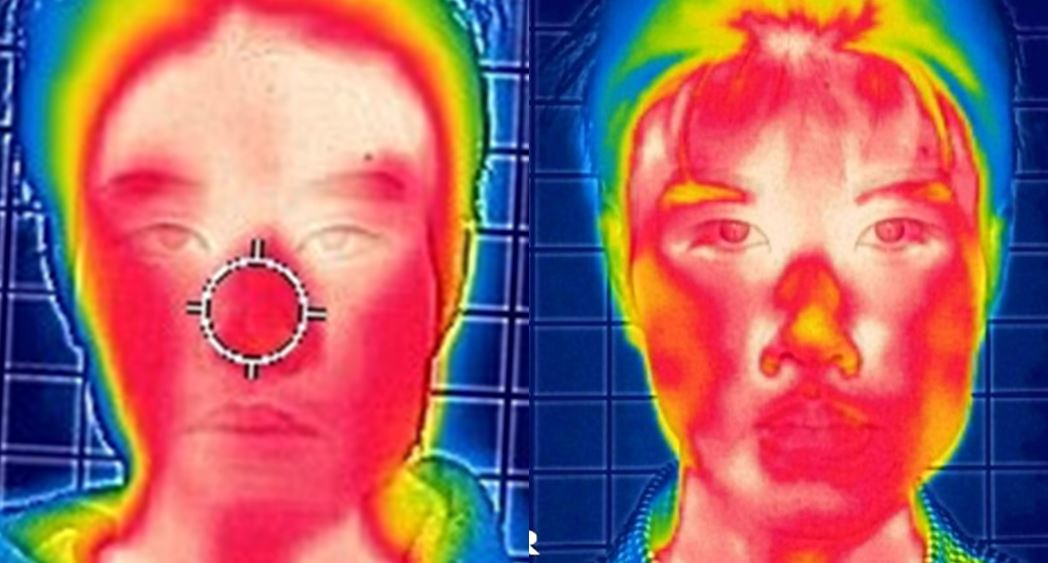

When the three-dimensional position of the mandible is aligned with the facial midline and the teeth are arranged accordingly, the following changes occur.